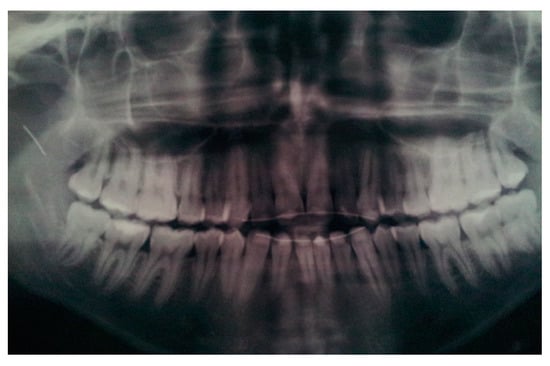

| Case 2 Impacted teeth in Pfeiffer Syndrome | 0.5 mm | 0.3 mm | 0.6 mm | |

| Case 3 Impacted teeth in Apert Syndrome | 0.3 mm | 0.5 mm | 0.4 mm | 0.5 mm |

| Case 4 Impacted teeth | 0.3 mm | 0.2 mm |